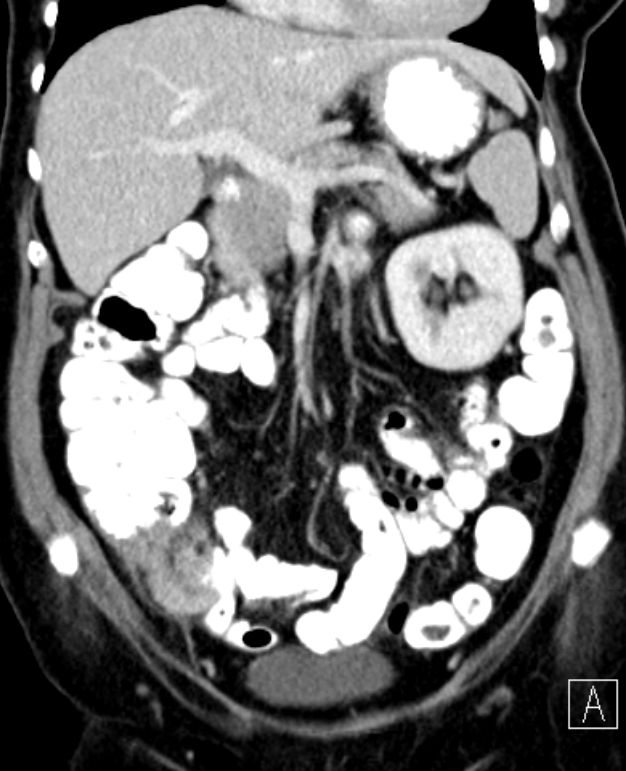

Ausgehend von zökumnahen Anteilen des Wurmfortsatzes,

Infiltrate eines zum Teil tubulär, zumeist kribriform und strangfrömig wachsenden malignen epithelialen Tumors.

Dieser bricht unter fibroplastischer Stromatransformation in das perimuskuläre Fettgewebe aus und infiltriert sekundär die Dünndarmwand.

CDX 2: kräftige Kernfärbung. Zytokeratin 20 z.T. gefärbt. Zytokeratin 7, Chromogranin, Synaptophysin negativ.![]() |